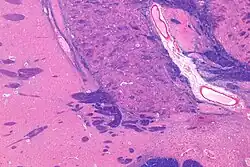

The substantia innominata, also innominate substance or substantia innominata of Meynert (Latin for unnamed substance), is a series of layers in the human brain consisting partly of gray and partly of white matter, which lies below the anterior part of the thalamus and lentiform nucleus. It is included as part of the anterior perforated substance (as it appears to be perforated by many holes which are actually blood vessels). It is part of the basal forebrain structures and includes the nucleus basalis. A portion of the substantia innominata, below the globus pallidus is considered as part of the extended amygdala.[1]

In the late 20th century following improved imaging by staining it was reclassified as part of the striatopallidal system, which is made up of the dorsal striatum and dorsal pallidum, and the ventral striatum and ventral pallidum.[2][3]